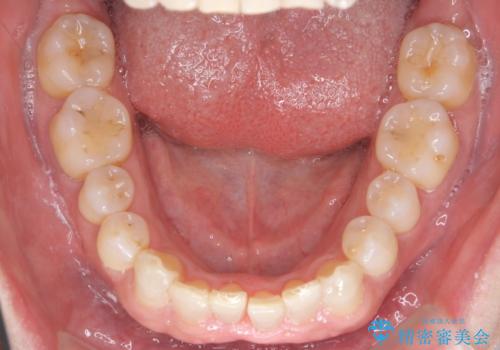

八重歯と下の歯のがたつき マウスピースで

- 右上の犬歯が目立つのが気になる、下の歯並びも治したいとのことで来院。

歯を抜かずに少し削って小さくして並べました。

並びも良くなり、患者様にも喜んでいただきました。

右上の犬歯の歯肉退縮自体は進行する可能性をお伝えしておりましたが、特に変化なく治療できました。